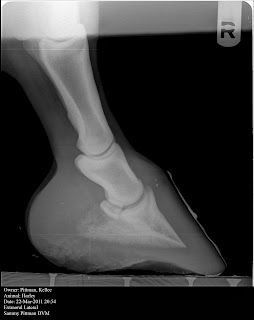

Same story as the right but a greater increase in sole depth but still not easily notable . Below is a couple of the venogram shots. I labeled a few important aspects. We are only doing venogram on the left front at this point. I definitely notice a change in the terminal papillae, in that they are becoming longer and more robust. This should be more obvious at sole depth increases. I realize everyone that may read these may not understand all the lingo and importance involved. If you have specific questions please comment and ask! We also took radiographs of my wifes mare, Harley, which has never had shoes and has been in a paddock/stall for most of her life and she has amazing feet and maintains great sole depth. I will add in her radiographs at the bottom as well.. Thanks and please come back for more reading.